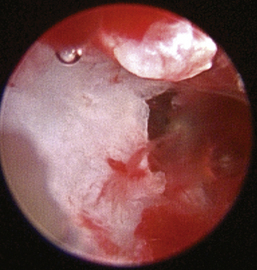

The middle ear consists of an air-filled tympanic cavity, three auditory ossicles, and the tympanic membrane. The tympanic membrane is located at a 45-degree angle in relation to the central axis of the horizontal part of the external ear canal. The tympanic membrane is a semitransparent membrane that separates the external ear canal from the middle ear, is thin in the center and thicker at the periphery, and is divided into two sections, the small upper pars flaccida and the larger lower pars tensa (Figure 20-2). The pars flaccida is the pink, small, loosely attached region forming the upper quadrant of the tympanic membrane that contains small blood vessels. The pars flaccida is usually flat; however, even in the healthy ear one may identify a bulging pars flaccida (Figure 20-3). The exception is the Cavalier King Charles Spaniel, in which a bulging pars flaccida may be indicative of a disease known as primary secretory otitis media (PSOM) (Figure 20-4).

image

Figure 20-4 Bulging pars flaccida in a Cavalier King Charles Spaniel with primary secretory otitis media (PSOM). 1, Pars flaccida.

(Courtesy of Dr. Lynette Cole, The Ohio State University, Columbus, Ohio.)